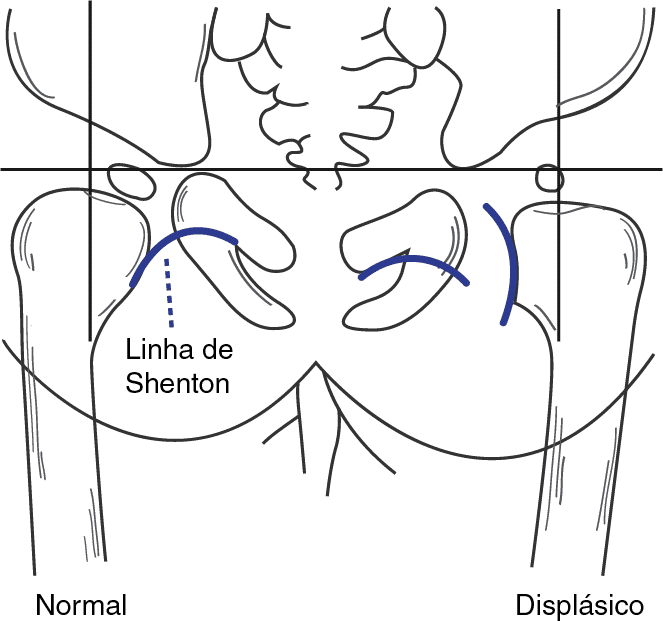

Texto alternativo para a imagem

Descrição da ilustração: Representação esquemática da linha de Shenton. Trata-se de uma linha traçada entre a borda medial do colo femoral e a borda superior do forâmen obturador. Ela deve ter um contorno contínuo. Nos casos de ascensão da cabeça femoral (luxação), esta linha sofre solução de continuidade.

• Linha (arco) de Shenton: É uma linha traçada entre a borda medial do colo femoral e a borda superior do forame obturador. Ela deve ter um contorno contínuo.